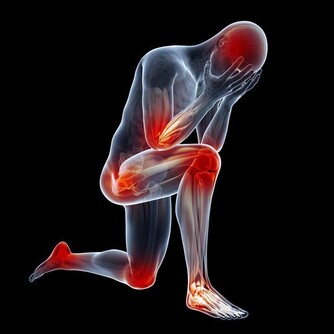

(3)心腦血管疾病

高尿酸血症是心腦血管系統疾病的獨立危險因素。

據臨床調查:

高尿酸血症患者高血壓病發生率為8.1%-13.6%;糖尿病為5.1%-15.7%;

高脂血症為32%-66.5%;冠心病為3.2%-6.3%;腦梗死為0.46%。